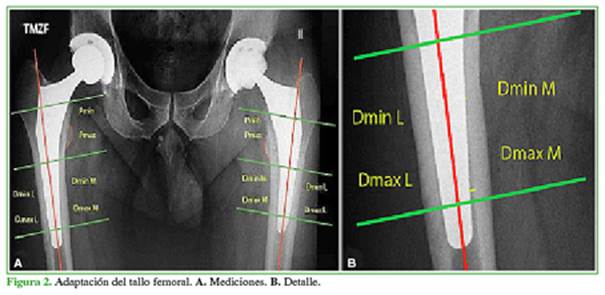

La adaptación del tallo femoral se evaluó en dos zonas: la región proximal (zona de recubrimiento de hidroxiapatita) y la región distal (zona desde la finalización del recubrimiento de hidroxiapatita hasta 10 mm proximal a la punta del tallo femoral). Se midió la brecha medial en la región proximal entre el tallo femoral y la cortical medial, y se obtuvo la distancia mínima (Pmin; mínima distancia desde la cortical medial hasta el implante) y máxima (Pmax; máxima distancia desde la cortical medial hasta el implante). En la región distal, se registró la brecha medial y lateral entre el tallo femoral y la cortical, y se obtuvo la distancia mínima (Dmin M; mínima distancia desde la cortical medial hasta el implante) y máxima (Dmax M; máxima distancia desde la cortical medial hasta el implante) medial y lateral (Dmin L; mínima distancia desde la cortical lateral hasta el implante y Dmax L; máxima distancia desde la cortical lateral hasta el implante) (Figura 2).